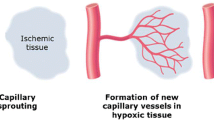

Angiogenesis, in general, is the physiological process by which new capillaries are formed from pre-existing vessels. Formation of new microvascular networks can be of critical significance in the setting of cardiovascular disease, as angiogenesis can assist in restoring blood flow and perfusion to skeletal muscle or cardiac tissue exposed to hypoxic conditions and potentially prevent the onset of tissue necrosis. Angiogenesis is regulated through multiple angiogenic factors, cells, and the extracellular matrix (ECM), and can be stimulated in the setting of various conditions that may be associated with cardiovascular disease, such as ischemia, hypoxia, inflammation, and alterations in vascular shear stress [5]. The process of angiogenesis can be described by several stages. These stages are first characterized by the initial activation of endothelial cells that leads to increased permeability and proliferation of endothelial cells. Next, the extracellular matrix (ECM) is degraded, with the assistance of multiple factors such as matrix metalloproteinases (MMPs) and integrins, which facilitates infiltration of endothelial cells. Following ECM breakdown and endothelial cell migration, the development and eventual stabilization of a new capillary occurs [6].